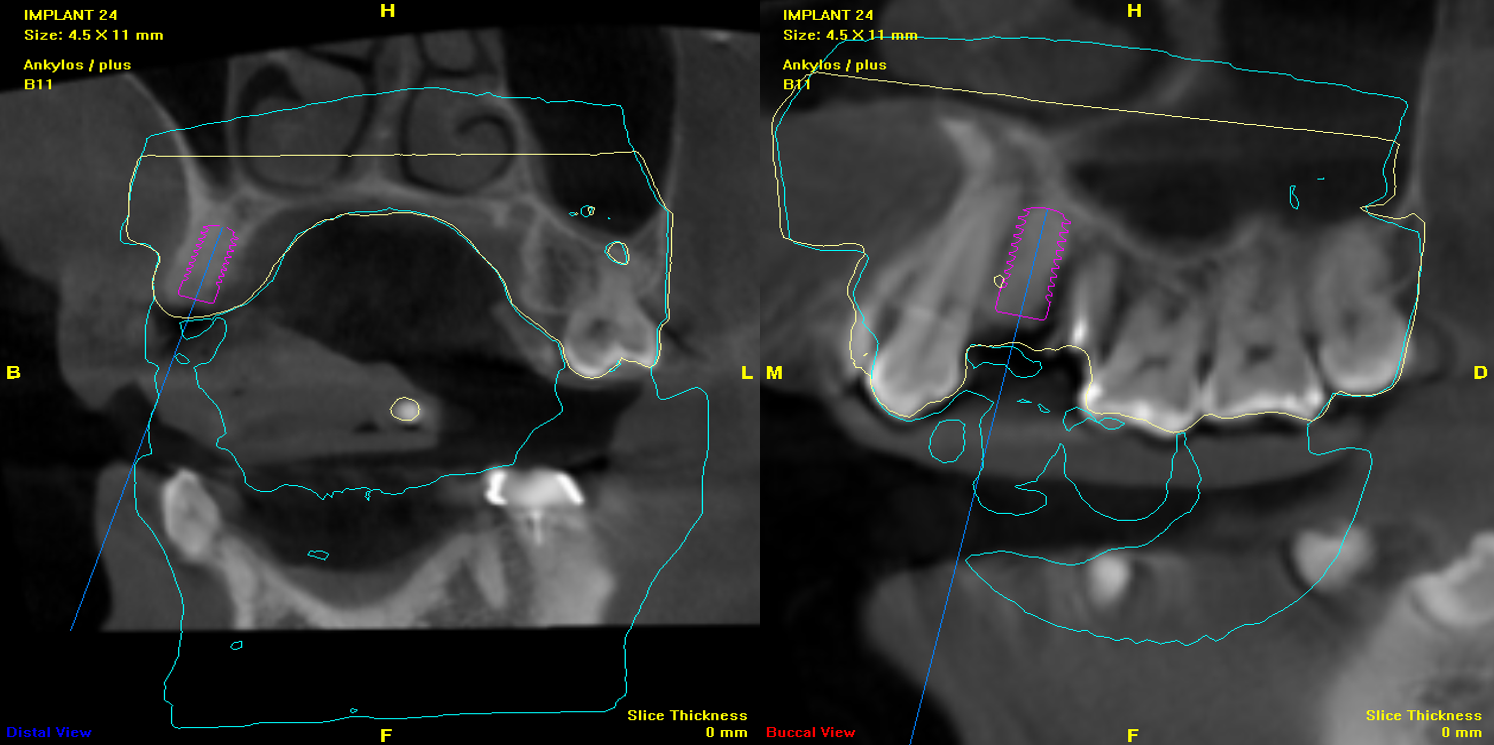

植牙導航模擬

2)電腦定位手術模板